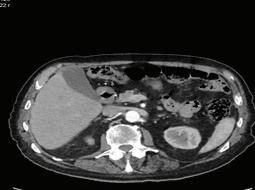

66 БЪБРЕЧНО-КАМЕННА БОЛЕСТЕТИОЛОГИЯ, ЧЕСТОТА, ЛЕЧЕНИЕ И ПРОФИЛАКТИКА В. Василев, Н. Димитров